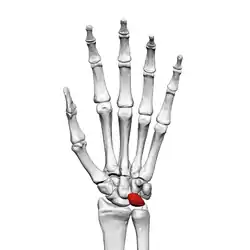

Lunate bone

The lunate bone (semilunar bone) is a carpal bone in the human hand. It is distinguished by its deep concavity and crescentic outline. It is situated in the center of the proximal row carpal bones, which lie between the ulna and radius and the hand. The lunate carpal bone is situated between the lateral scaphoid bone and medial triquetral bone.

Lunate bone of the left hand (shown in red). Animation.